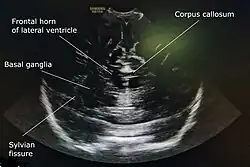

Cranial ultrasound is a technique for scanning the brain using high-frequency sound waves. It is used almost exclusively in babies because their fontanelle (the soft spot on the skull) provides an "acoustic window". A different form of ultrasound-based brain scanning, transcranial Doppler, can be used in any age group. This uses Doppler ultrasound to assess blood flow through the major arteries in the brain, and can scan through bone. It is not usual for this technique to be referred to simply as "cranial ultrasound". Additionally, cranial ultrasound can be used for intra-operative imaging in adults undergoing neurosurgery once the skull has been opened, for example to help identify the margins of a tumour.[1]

A standard cranial ultrasound examination usually involves recording of approximately 11 views of the brain from different angles, six in the coronal plane and five in the sagittal and parasaggital planes.[7] This allows all parts of the ventricles and most of the rest of the brain to be visualised.